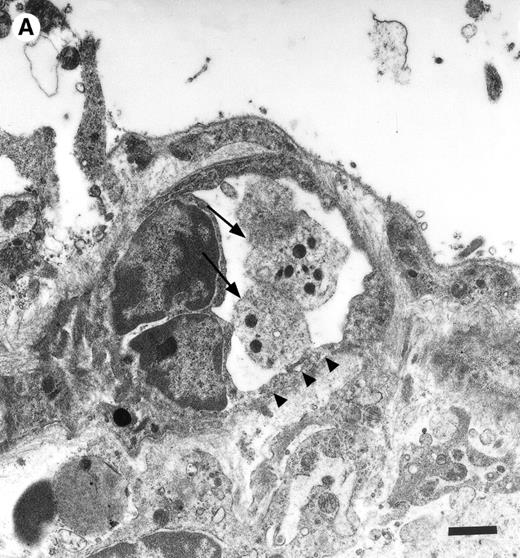

In the physiologic state without I/R, circulating platelets rarely interacted with the microvascular endothelium (Figs1 and 2). Few platelets were observed rolling along the endothelial cell lining of arterioles and postcapillary venules (0 ± 0 and 3 ± 1 platelets/s/mm, respectively). At the same time, only 26 ± 14 and 28 ± 11 platelets were found firmly attached per mm2endothelial cell surface of arterioles and venules, respectively. In contrast, 1.5 hours of ischemia dramatically enhanced platelet-endothelial cell interactions immediately after postischemic reperfusion (Figs 1 and 2). As reported earlier, postischemic platelet accumulation involved arterioles, as well as venules. More than 15 platelets/s/mm vessel diameter were seen rolling along the arteriolar and venular vessel wall, respectively. At the same time, the number of firmly adherent platelets had increased 20- and 12-fold in arterioles and venules, compared with sham-operated animals (Fig 1). Platelet aggregation was a prominent phenomenon. Electron microscopy demonstrated that single or aggregated platelets adhered directly to endothelial cells; obvious defects in the endothelial cell layer were not detected (Fig 3).

Platelets in postischemic microvasculature visualized by electron microscopy. There are no defects in the endothelial cell layer (arrowheads) Platelets (arrows) attach directly to endothelial cells (arrowheads). Bars represent 1 μm. Original magnifications: 7,000× (A) and 12,000× (B). NCL, endothelial cell nucleus.